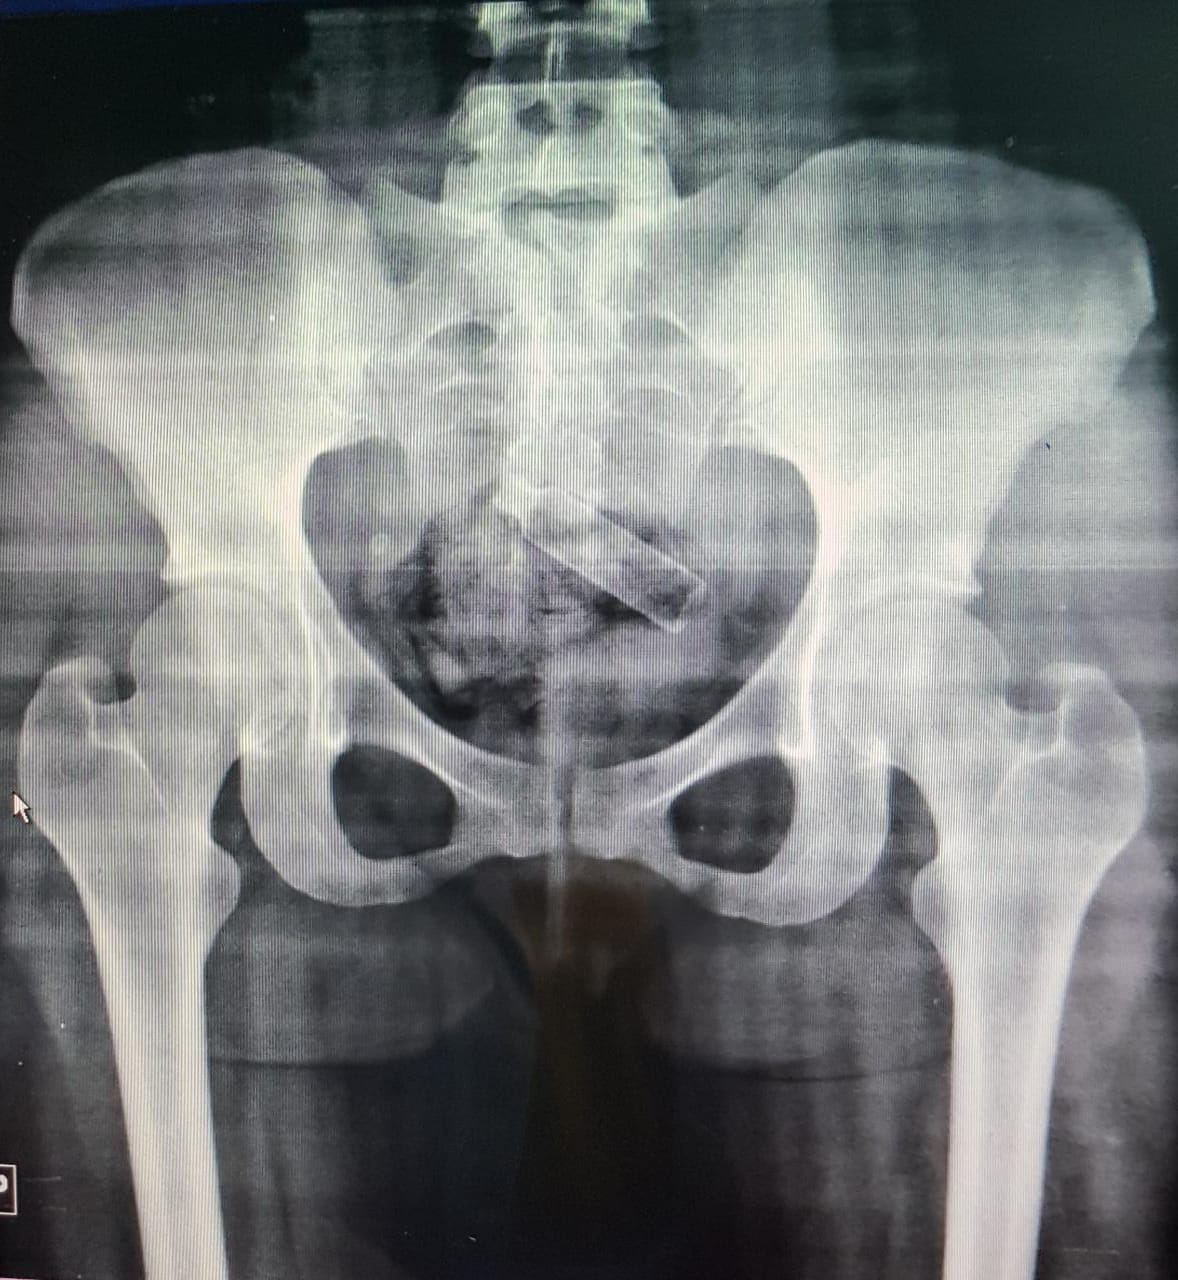

Ela foi conduzida para o Hospital de Urgência de Teresina (HUT) para a realização do exame raio-X, que identificou a droga escondida em sua região íntima.

A jovem passou por um procedimento, onde foram retirados três pacotes de maconha pesando 50 gramas e um recipiente de perfume da sua genitália.